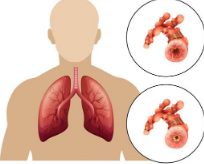

Asthma

a condition where the bronchial tubes become inflamed and as a result, restrict airflow